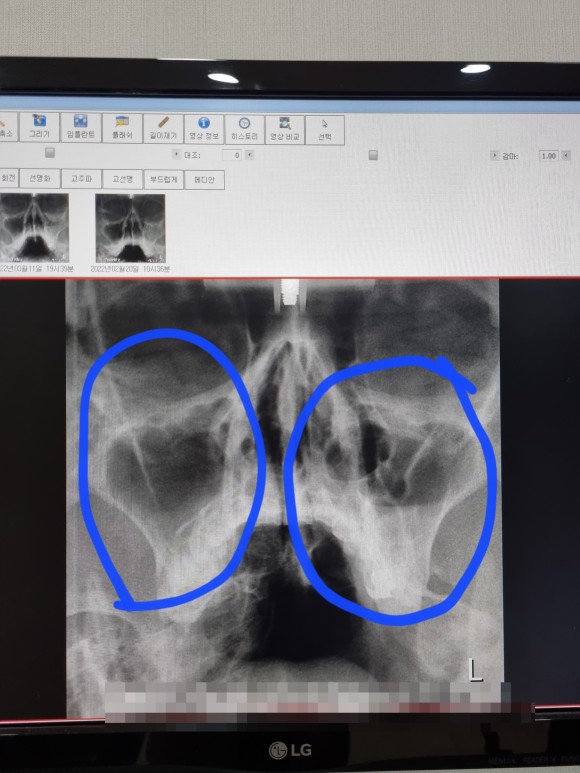

상태가 많이 호전된 것 같아 마지막 엑스레이를 찍어 보기로 했다.

부비강염

짜잔!

정말 많이 빠진 염증 아래 부분에 아주 적은 양만 남아 있다.

이번에는처음과마지막비교를해보니,

부비강염 완치

확연히 차이가 나는 두 사진!

엑스레이는 여기까지 찍기로 하고 마지막 일주일치 항생제를 더 먹고 치료를 끝내기로 했다.